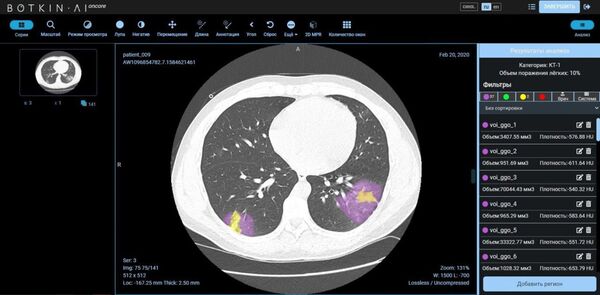

13:18 GMT 25.12.2020 (actualizado: 14:29 GMT 03.06.2024) Las empresas rusas Petrovax e Intellogic han lanzado un proyecto conjunto para prevenir y tratar la fibrosis pulmonar. Es una de las complicaciones más graves del COVID-19 que provoca insuficiencia respiratoria. En el proceso, se utilizan tecnologías de inteligencia artificial para determinar el grado de daño pulmonar.

"La investigación se analiza mediante un sistema basado en inteligencia artificial [redes neuronales] en varias etapas", dice Fomín.

Primero se realiza la selección de las zonas patológicas de los pulmones. Luego estas zonas pasan por una cascada de redes neuronales para determinar la especialidad de cada patología en particular. Al final, cuando todas las áreas afectadas son marcadas, se realiza una evaluación sumativa total de las lesiones.

Según el representante de la empresa, el algoritmo es fiable y prácticamente excluye la probabilidad de un error. En la etapa de aprendizaje para el sistema de redes neuronales fueron utilizados los "datos bien marcados", y el producto final se probó con éxito en condiciones reales.

La inteligencia artificial analiza los

daños en el tejido pulmonar y pasa el análisis en cuestión de dos a cinco minutos, pero el tiempo total del estudio puede variar y depende del "tipo y características de la integración realizada, así como de la calidad del estudio".

El interlocutor de Sputnik asegura que la plataforma de Botkin.AI está "completamente lista" para prestar la ayuda a los radiólogos. Esta solución innovadora "tiene precios accesibles" y por eso puede ser implementada para el uso amplio, tanto en las clínicas de Rusia, como en cualquier otra parte del mundo.